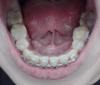

Вот вид снизу!

Да и если верх выглядит еще более-менее, но низ просто кошмар!